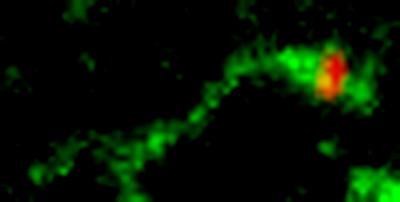

In Science , Linstedt and Mukhopadhyay report that Shiga toxin exploits this unique quality of GPP130 to its advantage. As it starts its return to the Golgi, GPP130 moves into a tubular extension off of the endosome's membrane and avoids being sent to the degradation pathway. Shiga toxin binds to GPP130, hitching a ride on a route that doesn't go to the lysosome. Instead, the toxin is carried to the Golgi apparatus and then to the endoplasmic reticulum, where it gets released into the cell's cytoplasm. It's here that it does its damage, shutting down protein synthesis and causing the cell to die.

Because Shiga toxin was dependent on GPP130 and manganese caused loss of GPP130, Linstedt and Mukhopadhyay decided to see whether manganese would protect against Shiga toxin infection. In cell cultures, manganese treatment yielded an almost 4,000-fold increase in the amount of Shiga toxin required to induce cell death. In a mouse model, mice exposed to a high dose of Shiga toxin and treated with non-toxic doses of manganese were 100 percent resistant to the toxin.